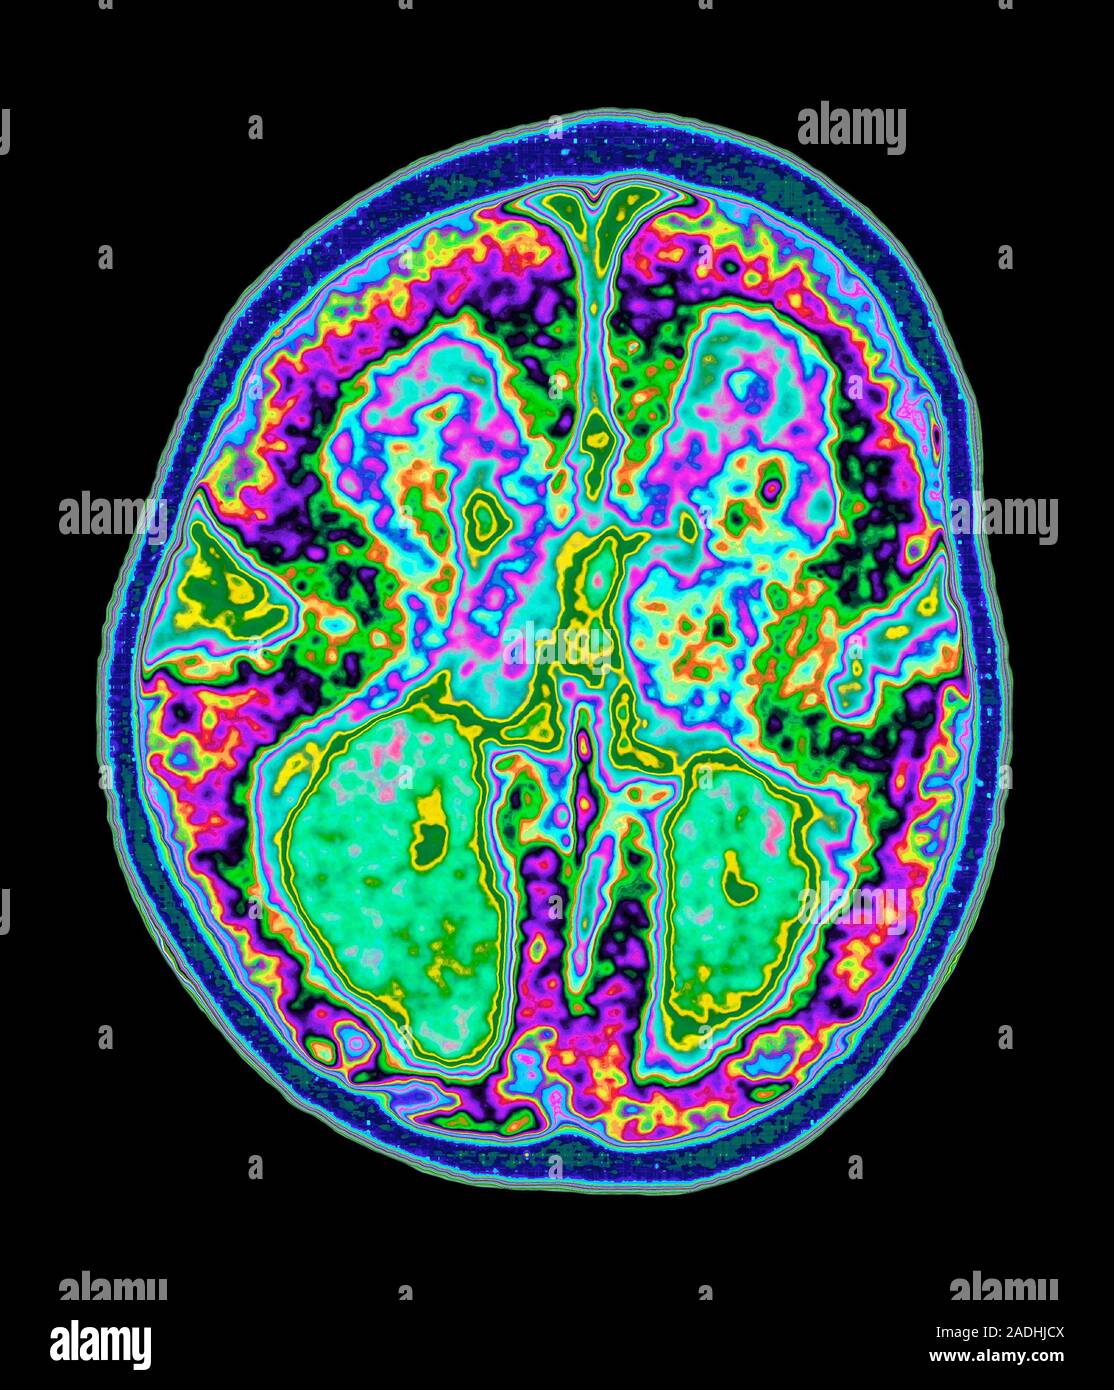

Мр перфузия

Мр перфузия 119 фотографий